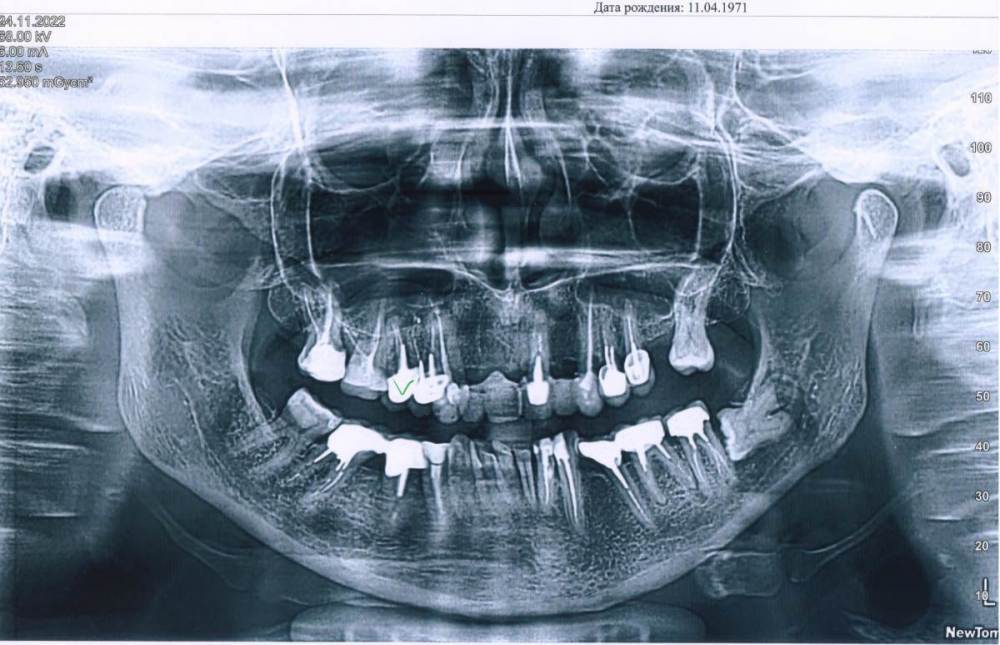

Svettala Опубликовано 28 ноября, 2022 Поделиться Опубликовано 28 ноября, 2022 Добрый день, уважаемые стоматологи, опять к вам за советом)). На снимке то, что имеем на сегодняшний момент, 5-ка справа будет удалена. Предлагают несколько вариантов поставить МК и куда, но хотелось бы выбрать самый оптимальный вариант. 1. Единый литой мост от клыка до клыка на шесть единиц. И мост с четверки до шестерки справа. Но тут минус, как сказал врач, что клыки могут со временем расшататься, так как очень большая нагрузка на них будет. 2. Установить на удаленную недавно единичку имплант и делать 2 небольших мостика от единицы до клыка справа и слева. Но вроде как в одну конструкцию нельзя совмещать свой зуб и имплант. 3. Поставить очень длинный мост от пятерки слева до шестерки справа и все сразу закрыть . Но этот вариант меня не очень устраивает, так как любая проблема хоть с одним зубом, то придется рушить всю конструкцию в 99% случаях. 4. Единый мост на шесть единиц как в 1-ом варианте , имплант на 5-ку и отдельно стоящие коронки на 4 и 5 зуб. Заранее спасибо, надеюсь на коллективную помощь)). Ссылка на комментарий

chervoncevdaniil Опубликовано 28 ноября, 2022 Поделиться Опубликовано 28 ноября, 2022 Не совсем понятно состояние клыка и 4 зуба слева,снимок,конечно не самого лучшего качества,но очень похоже что они плохие кандидаты как опора протяженного мостовидного протеза. Зубы и импланты в один мост соединять точно не следут. Все 4 плана,которые вам предложили,очень компромисные на мой взгляд,каждый с высоим риском осложнений Ссылка на комментарий

Bier Опубликовано 29 ноября, 2022 Поделиться Опубликовано 29 ноября, 2022 судя по всему под коронками там мало что осталось. Скажем так я вижу 2 варианта: 1. компромиссный - ставить единую конструкцию на то, что осталось. С пониманием "сколько простоит" 2. Удаление зубов с 5 по 5 и установка 4х имплантатов, соединенных единым протезом. Ссылка на комментарий

Bier Опубликовано 29 ноября, 2022 Поделиться Опубликовано 29 ноября, 2022 10 часов назад, Svettala сказал: Они ж крепкие и хорошие зубы. только правый. Левый уже нет. тогда первый вариант Ссылка на комментарий